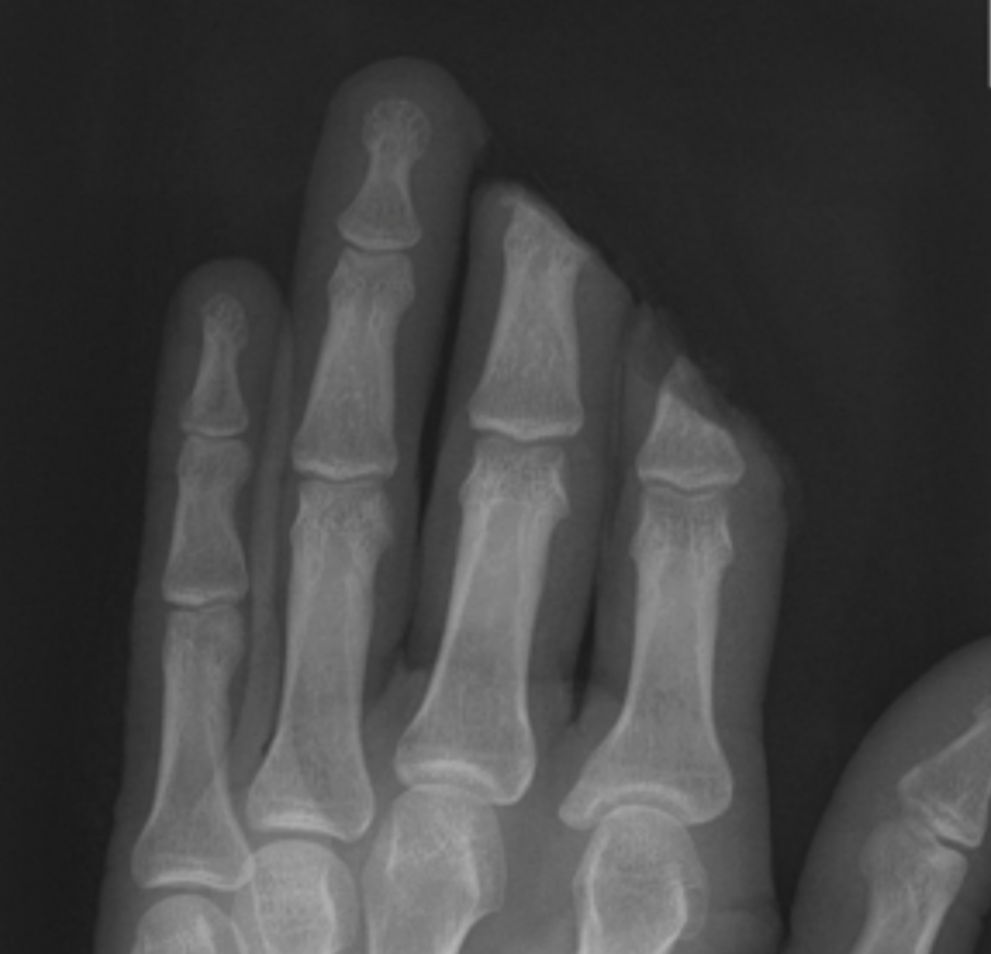

Replantacija je kirurški poseg, s katerim prišijemo od telesa popolnoma ločen (amputiran) del z vzpostavitvijo arterijske in venske prekrvavitve.

Replantacije na roki opravimo s pomočjo mikroskopa, saj je potrebno obnoviti pretok krvi v zelo drobnih žilah. Rezultat posega je odvisen od mehanizma poškodbe, pridruženih bolezni ter izkušenosti in znanja kirurga. Podoben poseg pri nepopolni amputaciji imenujemo revaskularizacija. Za končni uspeh je potrebno pravilno ukrepanje takoj po poškodbi. Nujnost ter način oskrbe sta odvisna od višine amputacije ter prisotnosti pridruženih poškodb. Čim več je v amputiranem delu mišic, tem krajše bo preživetje tkiva brez krvnega obtoka. Pri replantaciji z amputiranega in sprejemnega dela odstranimo vse mrtvo tkivo, učvrstimo kosti, zašijemo kite. Nato z mikrokiruško tehniko zašijemo žile in živce. Kožo direktno zašijemo ali vrzeli pokrijemo s kožnimi presadki. V kolikor replantacija zaradi lokalnih ali sistemskih dejavnikov ni mogoča moramo oblikovati amputacijske krne. Cilji oskrbe amputacijskih krnov so: zagotovitev zanesljivega in trajnega kožnega pokrova, ohranitev dolžine, obnovitev občutka za dotik, preprečitev kontraktur in bolečih nevromov, čimprejšnja vrnitev poškodovanca k vsakodnevnim aktivnostim.